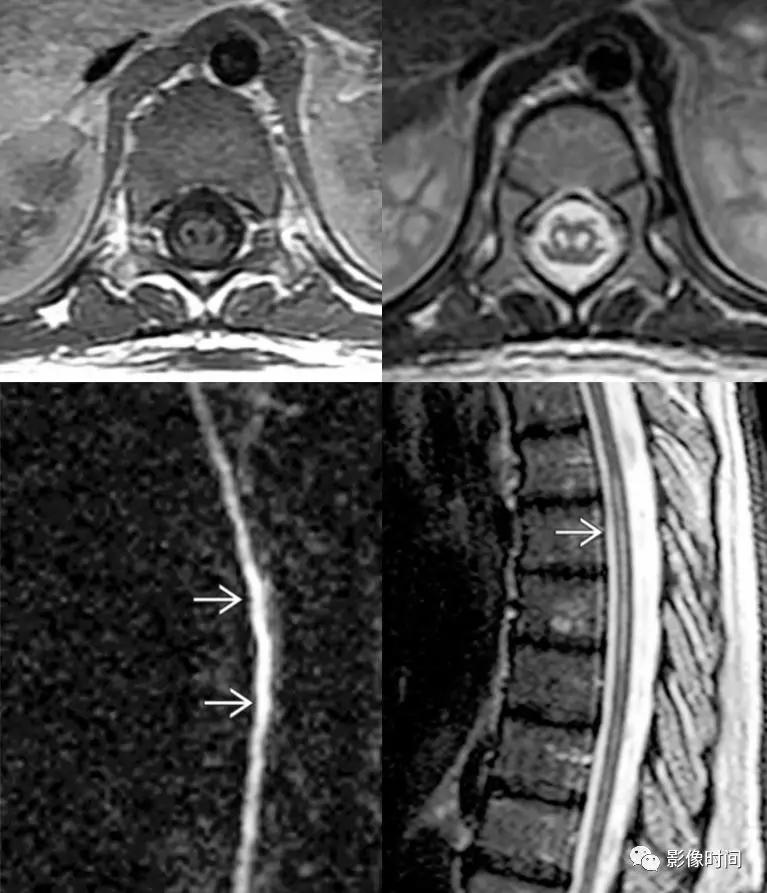

硬脊膜动静脉瘘 (spinal dural arteriovenous fistula,SDAVF):供应脊膜或神经根的细小动脉,在椎间孔处穿过硬膜与脊髓引流静脉相通,导致脊髓回流受阻。病因不明,成人-老年人胸腰段多见,缓慢起病,进行性加重。

MRI:

矢状位 T2WI 发现长节段高信号

矢状位 T2WI 脊髓周围流空低信号血管影

部分可见强化,提示血脑屏障破坏

脊髓内长节段T2WI高信号,髓周可见多发点状流空血管,增强扫描出现强化